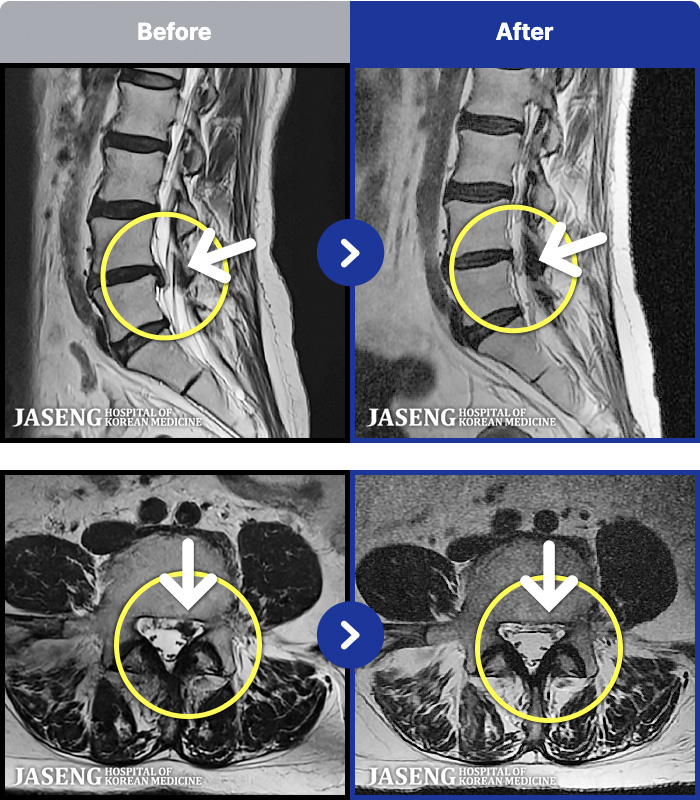

54 MRI ũ ʸ Ȯϼ.

[ϻ] 24.07.25~25.08.01